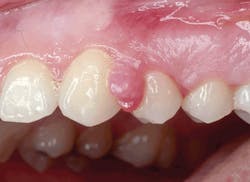

Figure 2: Pyogenic granuloma:

Courtesy of Drs. Michael Poth and David Klingman

The two represent very distinct histological characteristics but at times may display very similar clinical appearances while in certain stages of development. The pyogenic granuloma (PG) may become more fibrotic as the lesion ages, making it clinically resemble the peripheral ossifying fibroma (POF). The pyogenic granuloma often appears red and ulcerative and bleeds. The same can be true for the POF because they can become traumatized and may bleed.

Since these growths occur in exposed areas, they are often traumatized, highly vascular, and the surface area may present with bleeding or bright redness. The increase in capillaries and hyperplastic tissue cause the red color and increased size. The young pyogenic granulomas are usually very vascular and red, but the granuloma may become more fibrotic and more flesh-colored with age. When pyogenic granulomas occur during pregnancy, they tend to shrink or diminish altogether after common hormonal changes decrease. The PG is found on the gingiva in over 75% of cases, measuring anywhere from a few millimeters to a centimeter or more. The PG may also be found on the tongue, lips, and buccal mucosa. The anterior maxillary region is the most favored location.